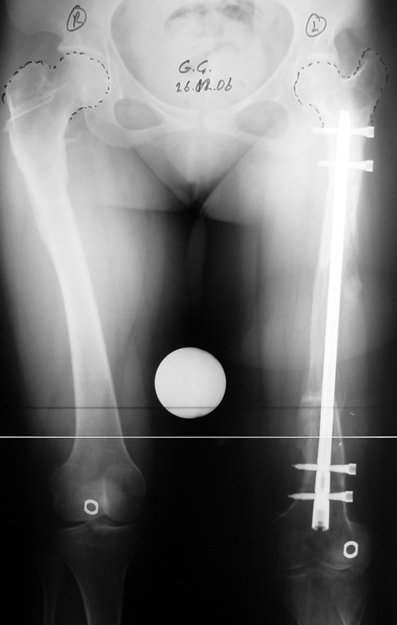

3. POSTTRAUMATIC LOWER LIMB SHORTNESS (MALUNION)

This type of shortness occurs after a fracture heals in a shortened position. Most cases are seen in adults and can be treated with one lengthening operation. Additional deformities can be corrected simultaneously. Most of these cases can be treated with lengthening over nail or just corrections and intramedullary nailing.